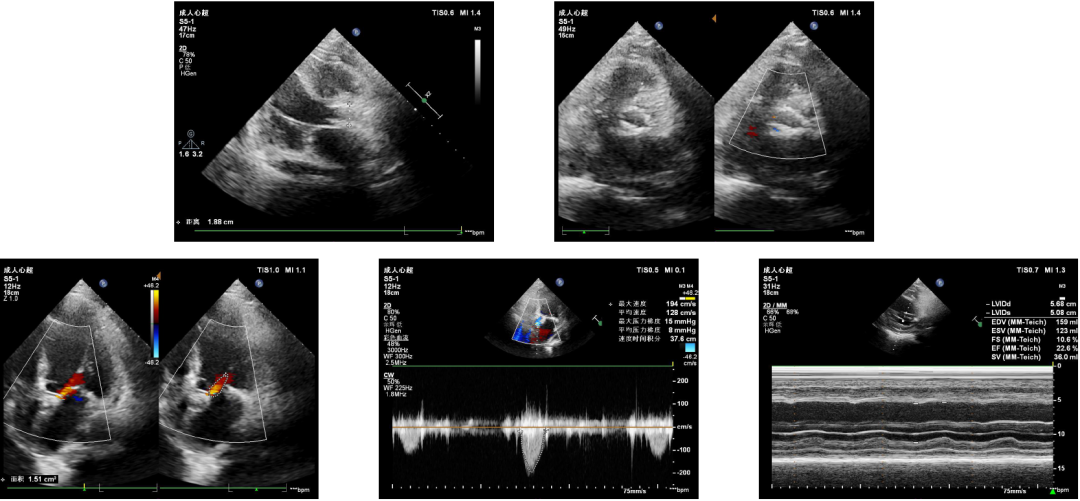

该患者为老年男性,半年余前活动后出现胸闷,呈压塞感,伴气促,多次外院治疗效果欠佳。入院前3天上述症状加重,端坐呼吸,不能行走,急诊拟“心力衰竭”收入住院。完善术前心脏彩超提示LVEF28%,主动脉瓣重度狭窄(瓣口面积0.42cm²,Vmax:359cm/s,MG:28mmHg)及轻度关闭不全,二尖瓣中-重度关闭不全,三尖瓣轻度关闭不全,肺动脉高压轻度。

术前心超